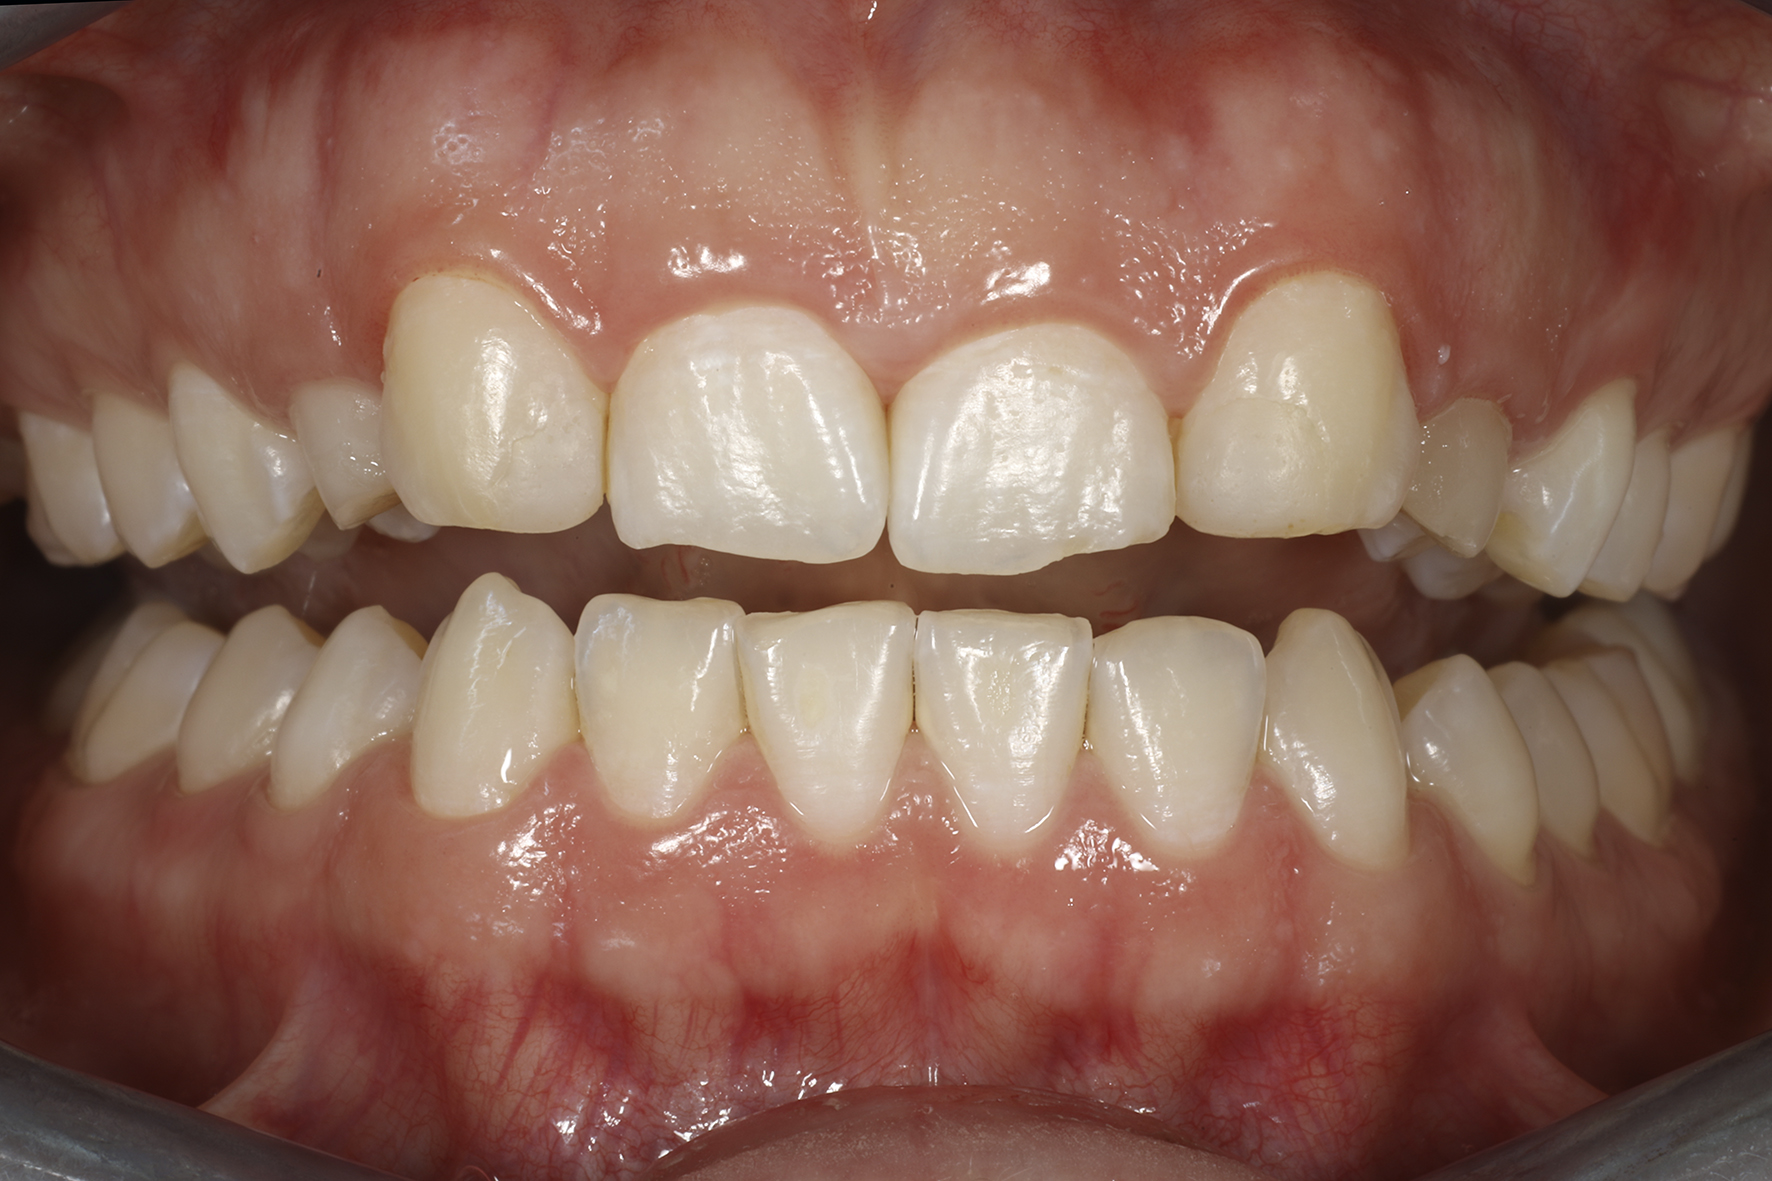

Lopputilanne 1/4. Implanttikruunut kulmahampaissa sekä ohuet keraamiset kuoret neljässä yläetuhampaassa paikoillaan.

Lopputilanne 2/4